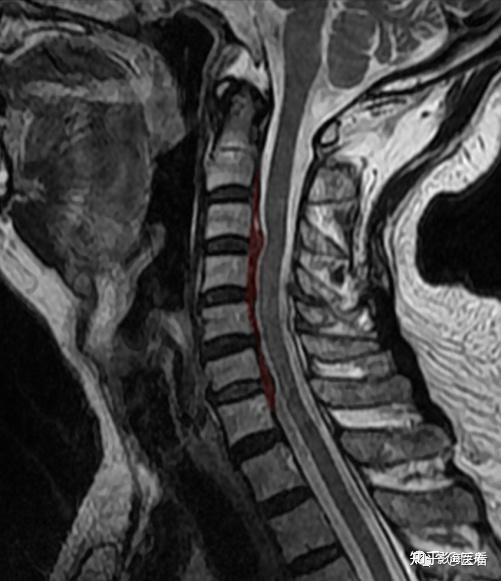

典型病例——颈椎后纵韧带钙化(mr) - 知乎

图片尺寸483x578